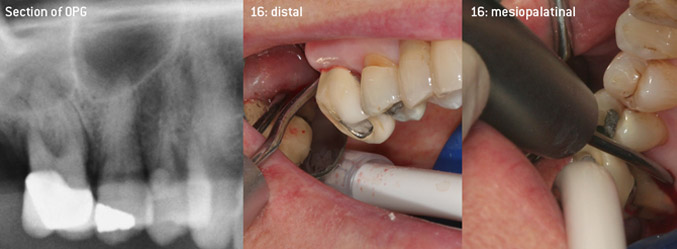

As initiators of the development of the new diamond-coated 3AP air scaler tip, the two dentists recognized the need for improvement of the handling restrictions of the commercially available diamond-coated tips, especially during furcation treatment and when working in tight intraosseous pockets. This should be possible for both non-surgical (Figure 2) and surgical (Figure 3) procedures.

The aim was to develop a universally applicable tip in order to avoid time-consuming tip changes. In addition, it should be easier to use the new working tips in tight intraosseous pockets from distal and at the distal furcation entrance of maxillary molars, allowing more effective use of instruments as a result. This was achieved by employing an instrument curve with a larger diameter (Figure 1), which is highly advantageous for closed debridement on teeth with advanced attachment loss and involvement of furcation in particular (Figure 4).